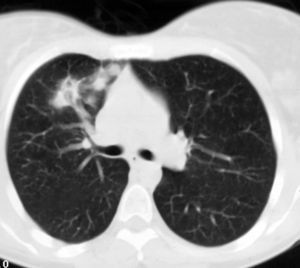

Mujer de 26 años de edad, fumadora de 10 cigarrillos al día, sin otros antecedentes de interés, que consulta por dolor torácico pleurítico sin fiebre, ni otra sintomatología acompañante. Las pruebas de laboratorio fueron normales. En la radiografía de tórax se observó una lesión redondeada de unos 3 cm en el lóbulo superior derecho, parahiliar (fig. 1). Ante la posibilidad de que se tratara de una neumonía redonda, recibió tratamiento antibiótico empírico con amoxicilina-clavulánico, sin cambios radiológicos. Se realizó una tomografía computarizada (TC) torácica sin contraste intravenoso, que mostró un nódulo pulmonar de bordes mal delimitados de 2 x 3 cm en el segmento anterior del lóbulo superior derecho, con tres nódulos satélites adyacentes (figs. 2 y 3). La fibrobroncoscopia fue normal. La citología del broncoaspirado y cepillado bronquial fue negativa para malignidad. Los cultivos para bacterias, hongos y micobacterias resultaron estériles. Se practicó una punción aspiración con aguja fina (PAAF) transtorácica bajo control con TC, obteniéndose material sin evidencia de malignidad. Ante la ausencia de diagnóstico y la imposibilidad para descartar malignidad se realizó una lobectomía superior derecha.

Fig. 3.--Tomografía computarizada helicoidal con cortes de 8 mm y ventana de parénquima pulmonar a nivel de la salida del bronquio del lóbulo superior derecho, muestra tres pequeños nódulos de contornos mal definidos adyacentes al nódulo pulmonar descrito en la figura 2.